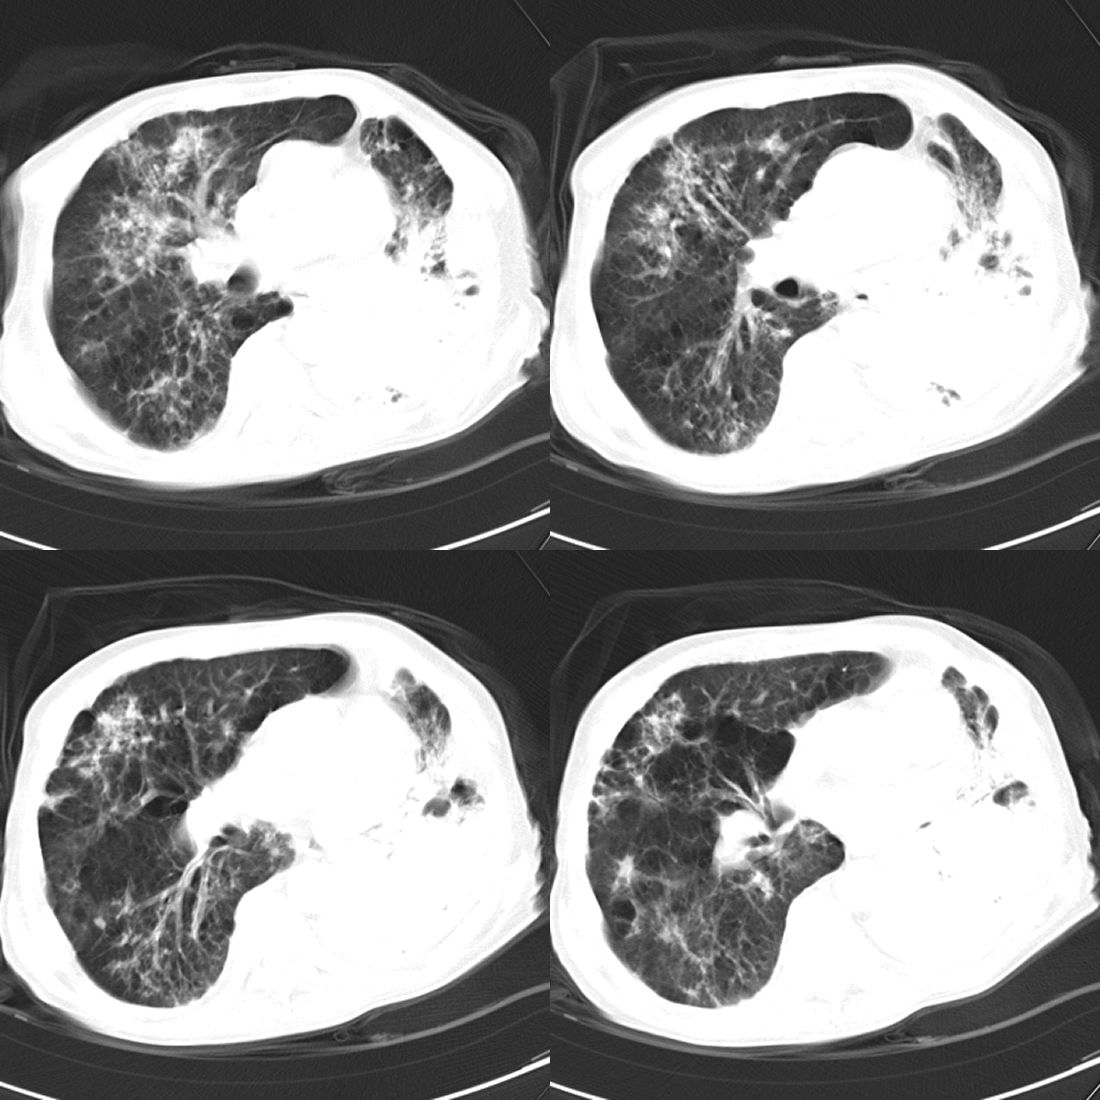

以下是引用zsl6918在2008-11-29 21:51:00的发言:[br]建议追问病史有无粉尘接触史,鉴别是结核还是矽肺。另外,左侧肺门的改变需强化明确,除外占位。

以下是引用liuyue在2008-11-30 6:01:00的发言:[br]双肺继发性肺结核;左侧包裹性积液;建议增强化或支气管镜检查除外左肺占位性病变.